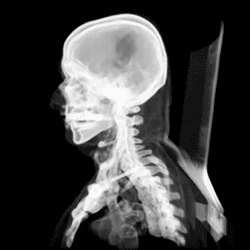

The skull, or cranium, is typically a bony enclosure around the brain of a vertebrate.[1][2] In some fish, and amphibians, the skull is of cartilage. The skull is at the head end of the vertebrate.

In the human, the skull comprises two prominent parts: the neurocranium and the facial skeleton,[3] which evolved from the first pharyngeal arch. The skull forms the frontmost portion of the axial skeleton and is a product of cephalization and vesicular enlargement of the brain, with several special senses structures such as the eyes, ears, nose, tongue and, in fish, specialized tactile organs such as barbels near the mouth.[4]

The skull is composed of three types of bone: cranial bones, facial bones and ossicles, which is made up of a number of fused flat and irregular bones. The cranial bones are joined at firm fibrous junctions called sutures and contains many foramina, fossae, processes, and sinuses. In zoology, the openings in the skull are called fenestrae, the most prominent of which is the foramen magnum, where the brainstem goes through to join the spinal cord.

In human anatomy, the neurocranium (or braincase), is further divided into the calvaria and the endocranium, together forming a cranial cavity that houses the brain. The interior periosteum forms part of the dura mater, the facial skeleton and splanchnocranium with the mandible being its largest bone. The mandible articulates with the temporal bones of the neurocranium at the paired temporomandibular joints. The skull itself articulates with the spinal column at the atlanto-occipital joint. The human skull fully develops two years after birth.